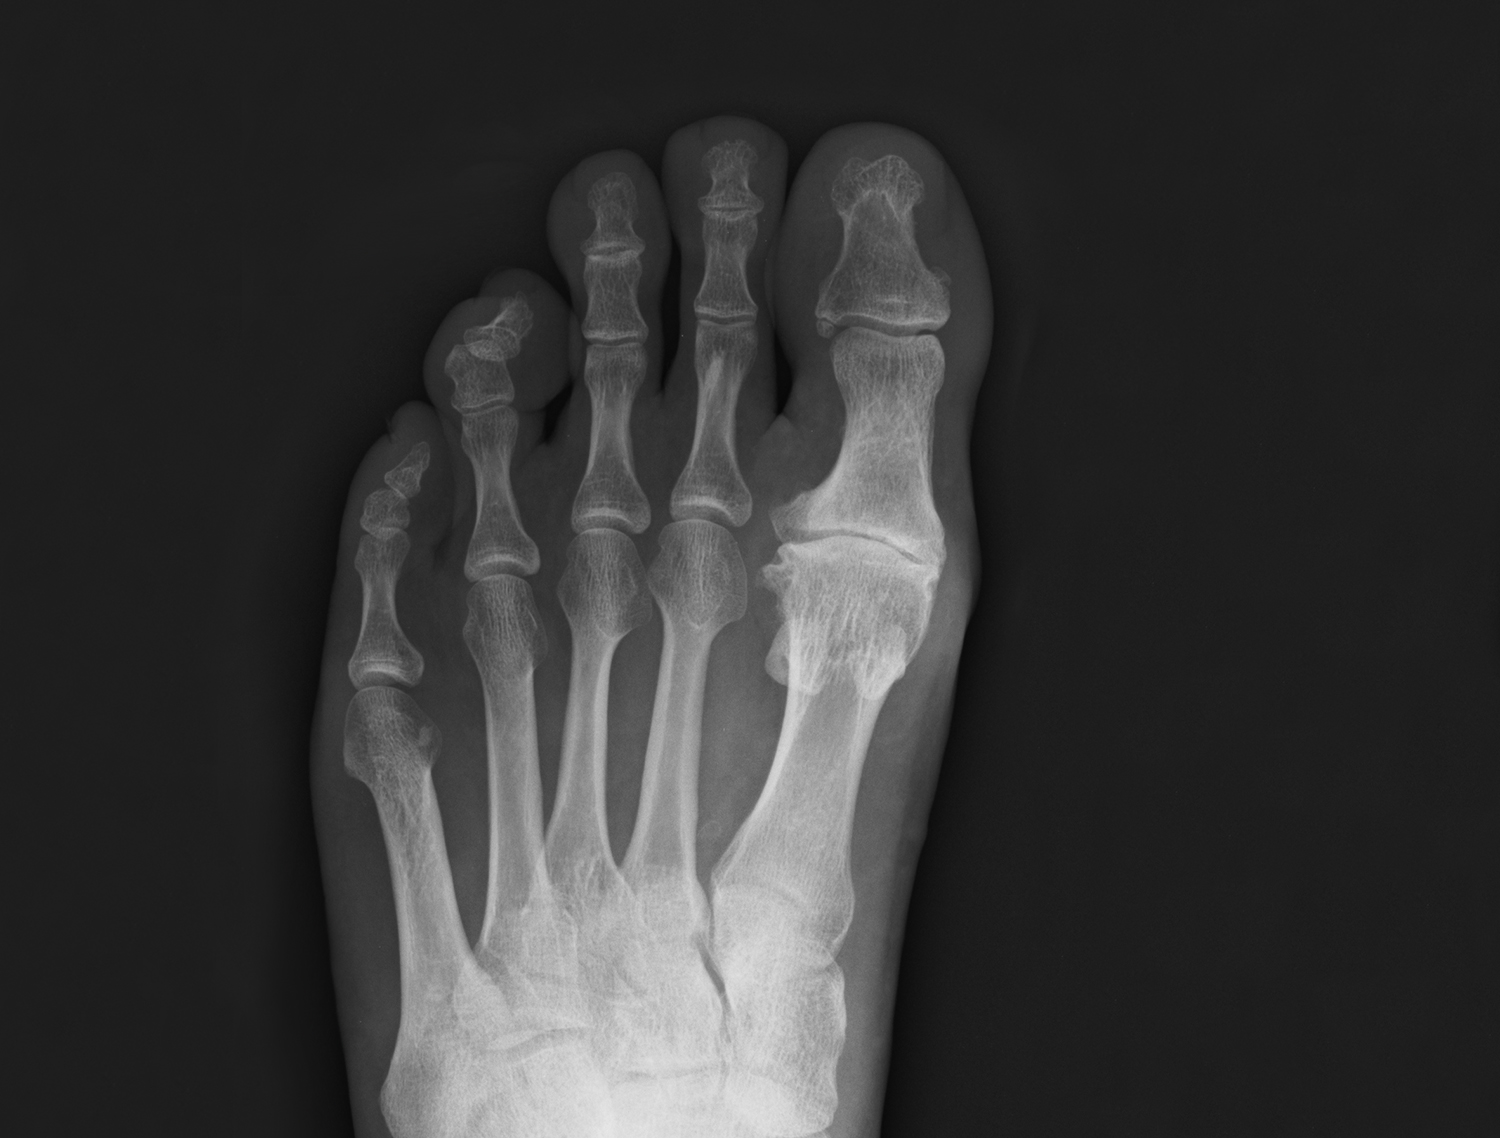

Bunion

Your big toe joint has moved out of alignment. This causes the big toe to turn towards your second toe causing a bony bump to stick out at the side of your foot. This bump may have become red and sore and is known as a 'Bunion'  Read more >>